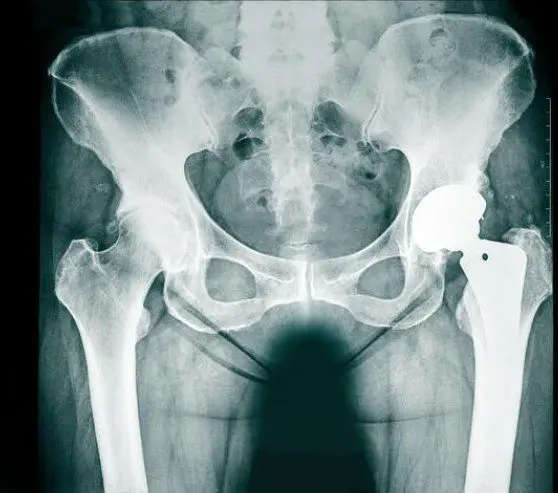

Die wichtigste Untersuchung zum Nachweis einer Arthrose ist neben der ärztlichen Untersuchung das Röntgenbild des Hüftgelenks.

Es werden immer eine Übersichtsaufnahme des ganzen Beckens und ein seitliches Hüftbild durchgeführt, um etwaige relevante Knochenformationen, Fehlstellungen, usw. zu erkennen, welche bei der Behandlung berücksichtigt werden müssen. Ausserdem muss für eine Operationsplanung eine Referenzkugel mit abgebildet sein, um die korrekte Skalierung des Bildes zu gewährleisten. Wenn Sie auswärtige Röntgenbilder mitbringen, die diesen Anforderungen nicht entsprechen, führen wir neue Aufnahmen durch.